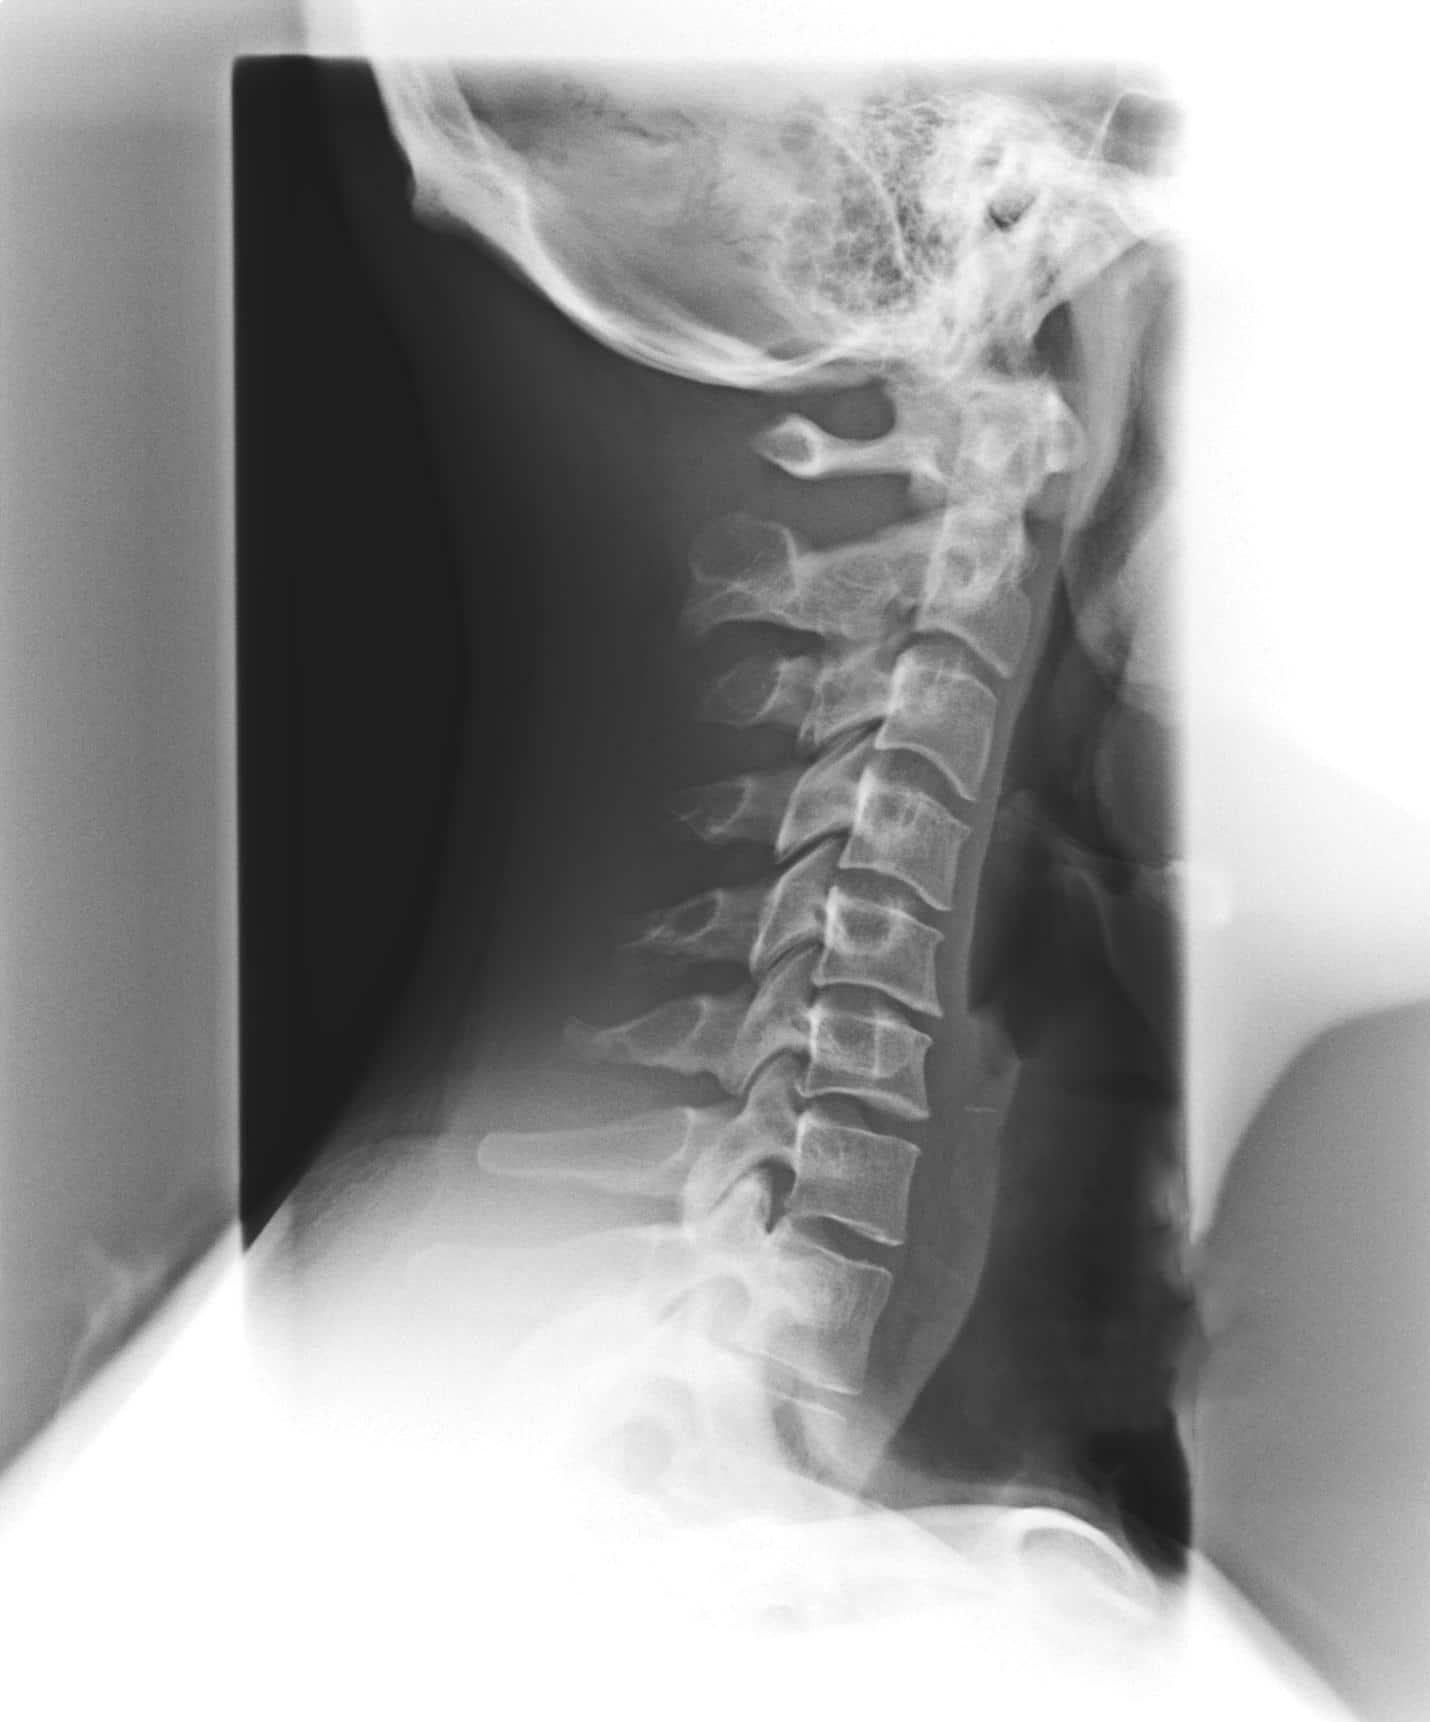

PHASE II Degeneration

Phase II of vertebral subluxation sees the Phase I misalignment continue further, with spaces between the discs beginning to narrow, the patient’s range of motion beginning to decrease, and certain stiffness and aches developing. At this point, prior damage may be irreversible, but chiropractic can help to restore functioning to near-normal levels.